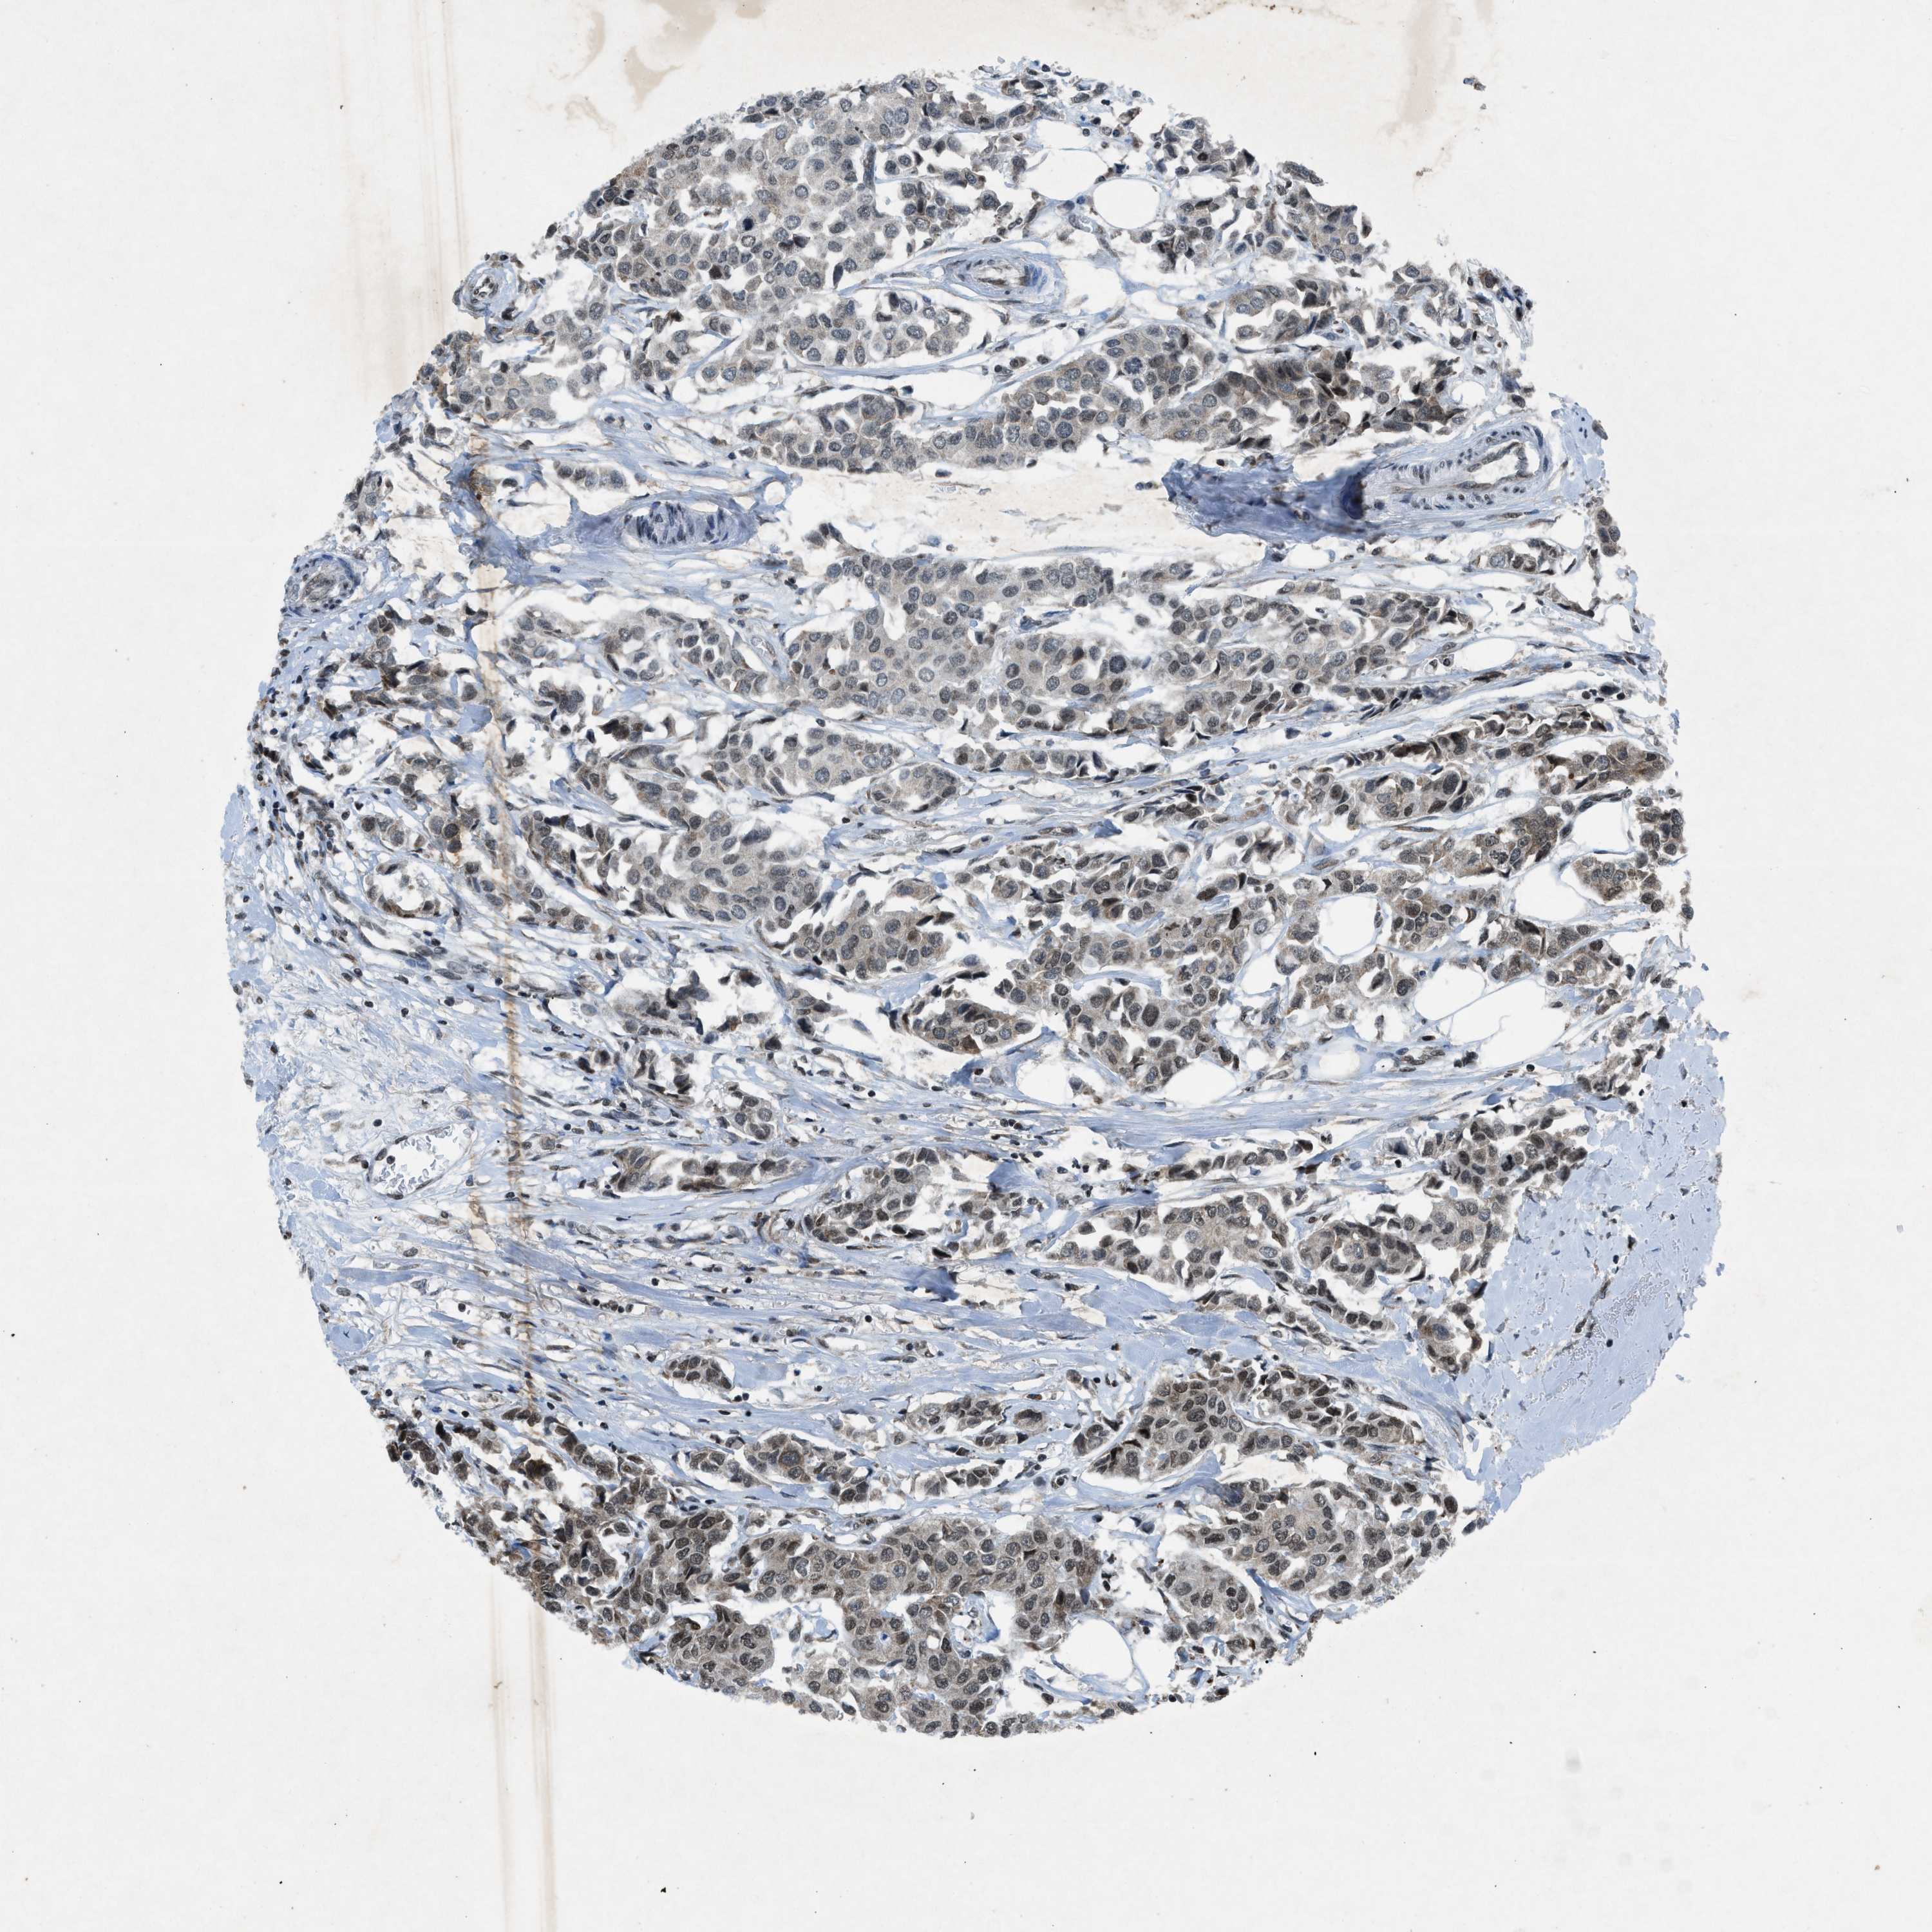

BRCA TCGA BRCA VALIDATION PROTEIN EXPRESSION